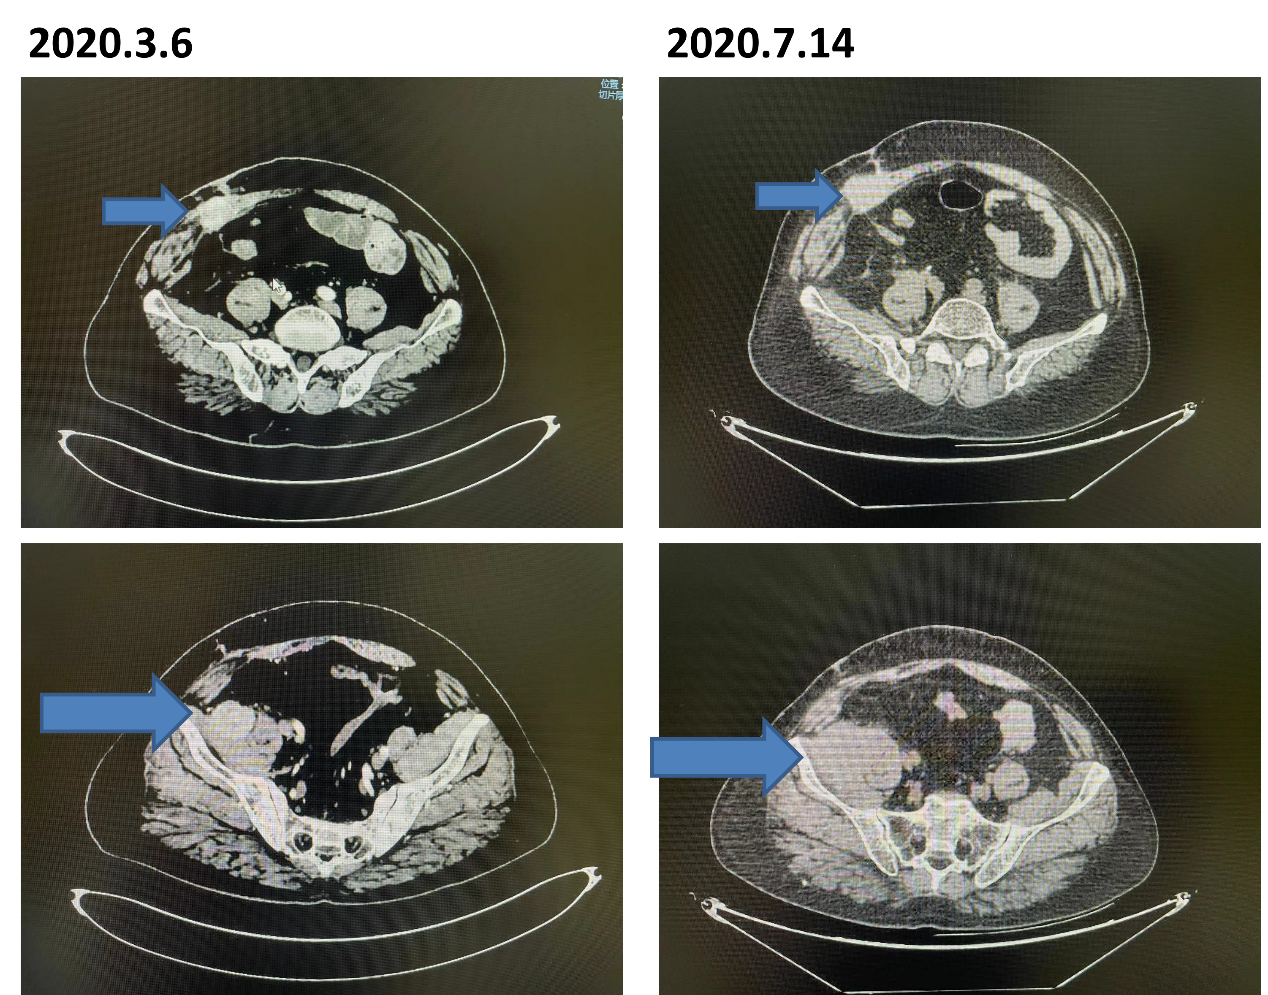

2020-07-13来院复查,胸部+泌尿系CT:1、右侧前腹壁、右侧髂窝近髂腰肌处、右侧腹膜多发占位,多考虑转移,与2020-03-07比较,病灶较前增大;2、腹膜后及右侧髂血管走行多发淋巴结显示。

18F-FDG:1、腹膜后肿大淋巴结影,考虑淋巴结转移,对比代谢程度增高;2、右下腹腹壁及右侧髂腰肌旁软组织块影,代谢活跃,考虑转移,对比代谢增高、部分病灶增大。

更新诊断:右肾癌根治术后腹壁转移 腹膜后转移 淋巴结转移(高危)。

考虑疾病进展,更换方案为阿昔替尼+特瑞普利单抗。

2020-12-16再次来院复查胸部+泌尿系CT:1、右侧腹膜、右侧髂窝近髂腰肌处占位,结合病史,多考虑转移,对比2020-07-14减小。

疗效评估PR,考虑治疗有效,持续阿昔替尼+特瑞普利单抗治疗。